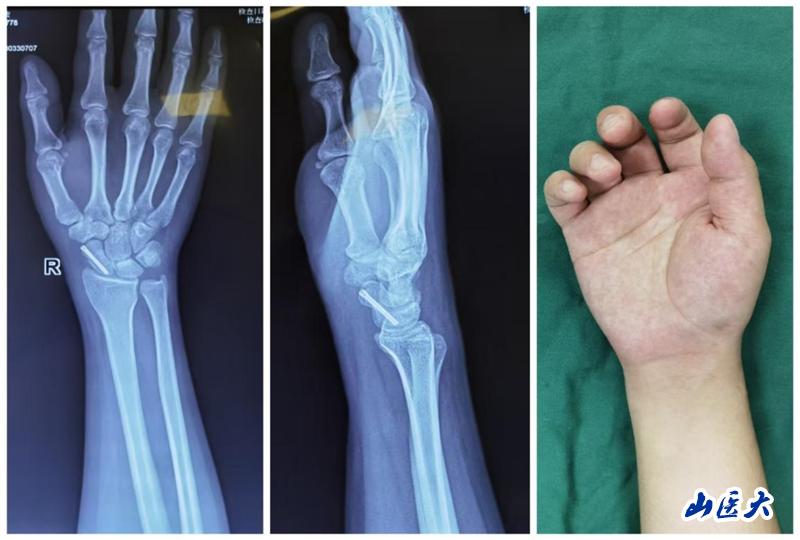

患者是一位年仅21岁的男性患者,他在上学途中不慎骑自行车摔倒,导致右腕部剧烈疼痛、肿胀并活动受限。经过X线片检查,确诊为右侧舟骨骨折。患者曾在重庆某三甲医院接受石膏固定术,但为寻求更专业的治疗,选择到我校第二医院西院区就诊。

考虑到患者年轻且希望尽快恢复,王建国团队在详细讨论并与患者及家属充分沟通后,决定采用微创经皮螺钉复位内固定术这一先进治疗方法。手术过程中,医疗团队借助C臂机透视引导进行精准定位,仅通过一个微小的2mm切口,就成功置入螺钉完成了内固定。术后,患者疼痛明显缓解,复查X线片显示螺钉位置良好,腕关节功能活动也恢复得相当不错。